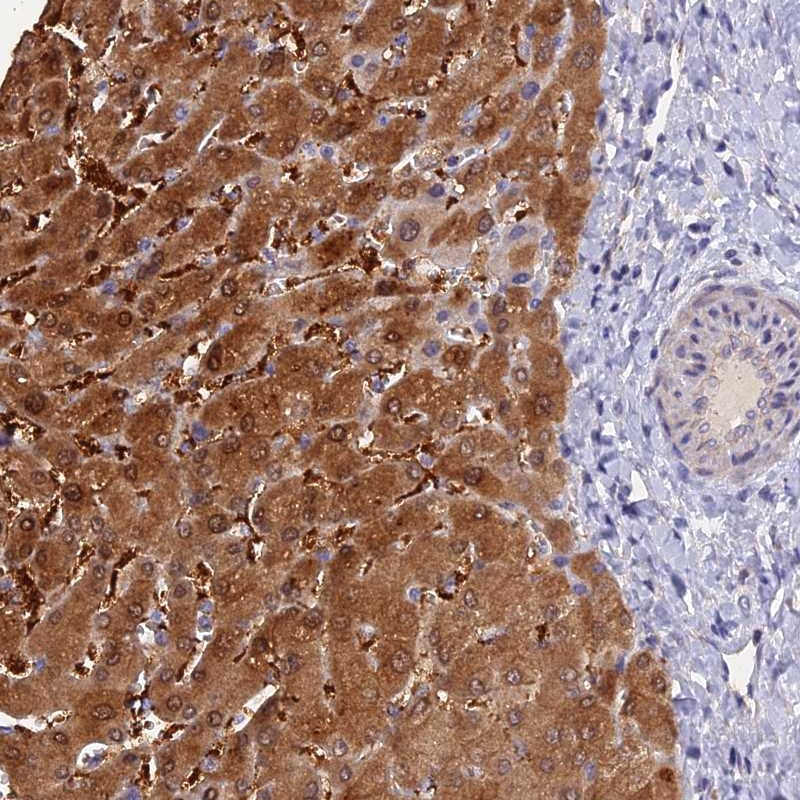

Immunohistochemical staining of human liver shows strong cytoplasmic and nuclear positivity in hepatocytes.